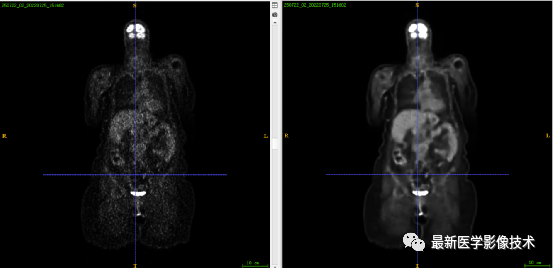

7.1、低剂量2重建结果

第一张是低剂量2的PET图像,第二张是full剂量PET图像,第三张是网络重建的PET图像。